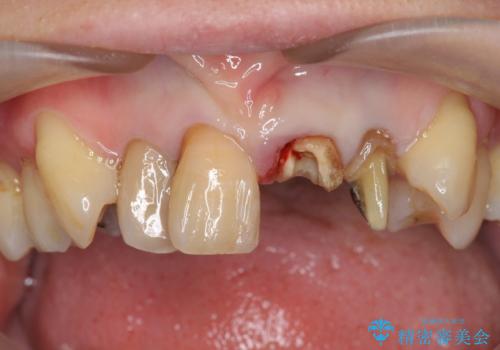

- 前歯のぐらつき、見た目の改善を希望され来院されました。

ぐらつきのある歯は、破折が認められ、その他前歯も不十分な根管治療や不適合なクラウン、レジン修復により審美障害が起きています。

問題を一つづつ丁寧に解決し、前歯の審美性の改善を計画します。

- 52.8万円(ジルコニアクラウン×4・仮歯×4)費用は治療当時の料金となります